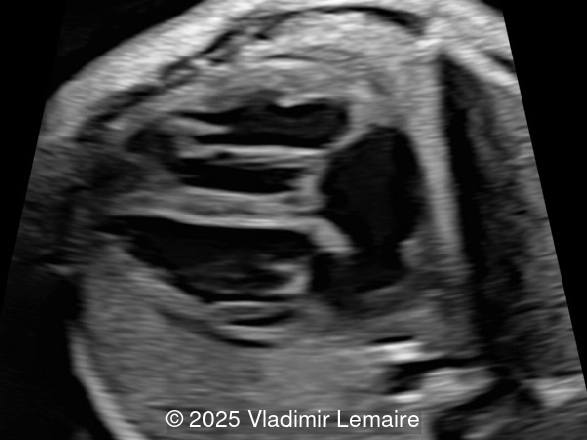

- Image 2: Axial plane of the fetal chest at the level of the four-chamber view. Note the normal appearance of the four-chamber view.

In Tetralogy of Fallot, the four-chamber view typically appears normal unless a large ventricular septal defect is visible in this plane. TOF is usually detected in the left ventricular outflow tract view, which demonstrates a perimembranous, subaortic ventricular septal defect with an overriding aorta. The overriding aorta is due to the discontinuity between the interventricular septum and medial wall of the aorta (malalignment VSD). This results in a partial connection of the aorta to the right ventricle, with an aorta that is slightly shifted to the right, referred to as aortic dextroposition. The aortic root appears dilated, especially in the third trimester, because it receives blood from both the right and left ventricles. The overriding aorta has a parallel course to the interventricular septum in contrast to the ascending aorta in a normal heart.